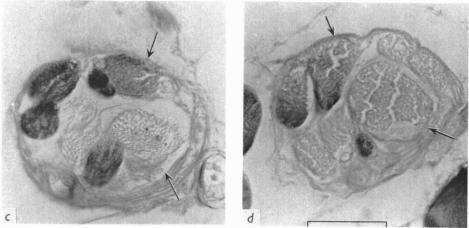

1. The distribution of static fusimotor fibres to intrafusal muscle fibres of cat peroneus longus muscle spindles was investigated using the glycogen-depletion technique of Edström & Kugelberg (1968). Single static gamma fibres were stimulation intermittently at high rates for 3 hr with the blood supply occluded for some of this time. Subsequently the portion of muscle containing the activated spindles was fixed, sectioned and stained for glycogen with the periodic acid-Schiff (PAS) method. 2. Ten static axons caused depletion in eleven spindles. In five of these the only glycogen-depleted fibres were nuclear chain fibres. In the other six spindles one nuclear bag fibre was depleted in addition to chain fibres and this was always the larger of the two within the spindle. 3. These results on a medium-sized hind limb muscle are compared with findings concerning the distribution of static gamma fibre axons previously investigated only in very small muscles. The results agree in showing that nearly all static gamma fibres innervate nuclear chain fibres but that in 50-75% of the times in which static gamma fibres innervate spindles the distribution is to bag fibres as well as to chain fibres. The interpretation to be put upon this is uncertain. One possibility with which the results from peroneus longus are consistent is that the bag fibres which are usually innervated by static axons are the 'intermediate' bag fibres whose ultrastructure has recently been shown to resemble that of chain fibres.

1. 采用埃德斯托姆和库格尔伯格(1968年)的糖原耗竭技术,研究了猫腓骨长肌肌梭的静态肌梭运动纤维向梭内肌纤维的分布情况。在部分时间阻断血液供应的情况下,以高频率间歇性刺激单根静态γ纤维3小时。随后,将含有被激活肌梭的肌肉部分固定、切片,并用过碘酸希夫(PAS)法对糖原进行染色。2. 10条静态轴突导致11个肌梭内的糖原耗竭。其中5个肌梭中,唯一糖原耗竭的纤维是核链纤维。在另外6个肌梭中,除链纤维外,还有1根核袋纤维糖原耗竭,且这根核袋纤维总是肌梭内两根核袋纤维中较大的那根。3. 将这些关于中等大小后肢肌肉的结果,与之前仅在非常小的肌肉中研究的静态γ纤维轴突分布的研究结果进行了比较。结果一致表明,几乎所有静态γ纤维都支配核链纤维,但在静态γ纤维支配肌梭的情况中,有50% - 75%的情况是同时支配袋纤维和链纤维。对此的解释尚不确定。与腓骨长肌的结果相符的一种可能性是,通常由静态轴突支配的袋纤维是“中间”袋纤维,其超微结构最近已被证明与链纤维相似。